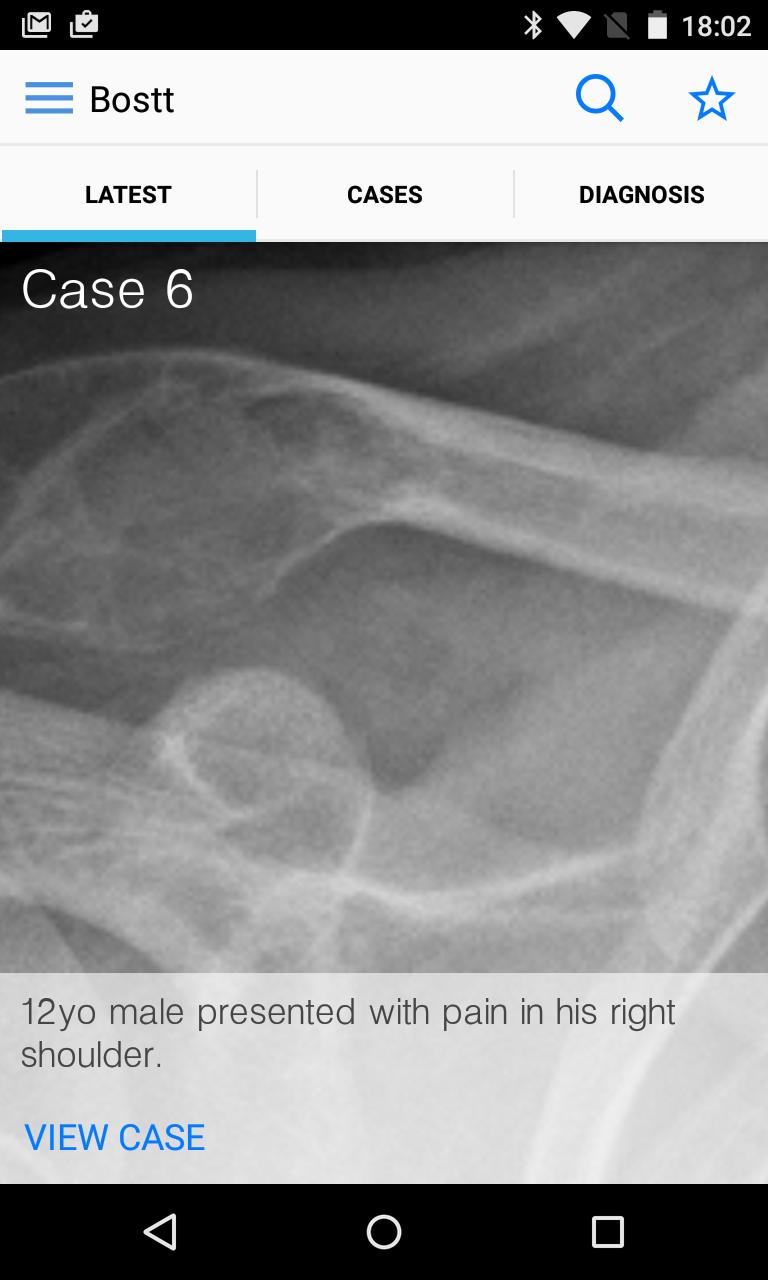

BoSTT bringt dem Benutzer eine echte Erfahrung mit häufigen und seltenen, typischen und ungewöhnlicheren Fällen von Knochen- und Weichgewebe -Tumoren. Jeder Fall hat eine klinische Anamnese, hochauflösende Radiologie- und Pathologie -Bilder, Diagnose, Behandlungs- und Lernpunkte.

Die App ist für medizinische Fachkräfte entwickelt, die im Bereich des muskuloskelettalen Gesundheitswesens arbeiten, einschließlich Radiologen, Pathologen, Orthopäden, Onkologen, Krankenschwester und Physiotherapeuten. Es kann auch von Medizinstudenten, Auszubildenden, Bewohnern und Fachkamen für die fortgesetzte medizinische Ausbildung verwendet werden.